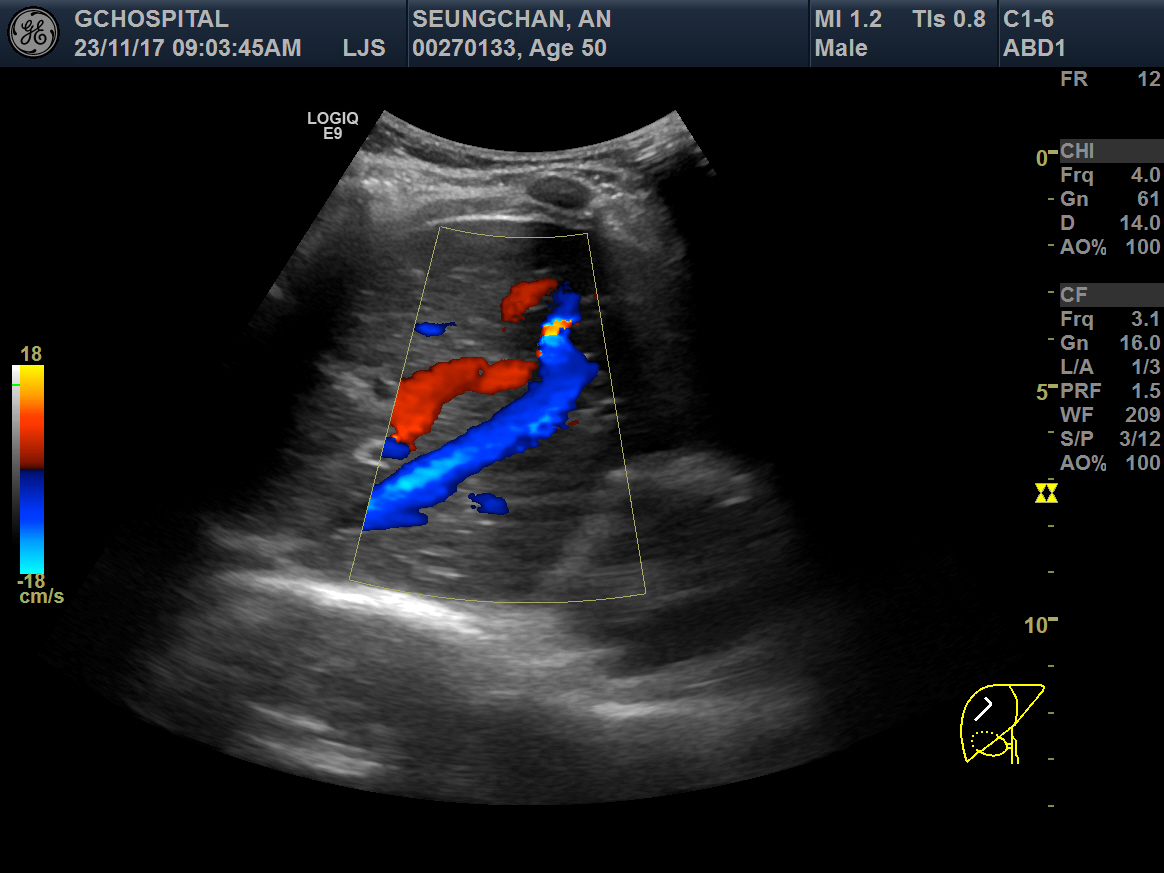

위의 두 영상은 간초음파에서 우간정맥(Rt. hepatic vein)의 장축을 따라 얻은 B모드 및 컬러도플러 영상입니다. 간실질 에코가 매우 거칠고 불균일한 만성 간질환 환자인데, 도플러영상에서 장축 전체에 걸쳐 뚜렷하게 확인할 수 있는 우간정맥이 B모드영상에서는 희미하게 일부분만 보입니다. 심지어 확인되는 부분도 컬러 도플러영상에서 보이는 것보다 훨씬 가늘어보이죠.

반면, 혈류가 반대방향이어서 빨갛게 보이는 간문맥(Rt. portal vein)의 경우는 B모드 영상에서도 간문맥 벽이 뚜렷하게 보일 뿐 아니라, 굵기도 컬러도플러 영상에서 확인되는 것과 별로 큰 차이가 나지 않습니다.

다음으로 중간정맥(middle hepatic vein)의 B모드 및 컬러도플러영상입니다. 컬러도플러영상에서 또렷하게 보이는 중간정맥이 B모드영상에서는 마찬가지로 매우 가늘고 희미하게 보입니다. 컬러도플러 영상에서 보여주는 중간정맥의 굵기가 실제 직경과는 차이가 있겠으나, B모드에서 보이는 것보다는 훨씬 직경이 클 것으로 보이며, B모드영상에서는 전혀 확인할 수 없었던 가지부분들도 컬러도플러영상에서는 또렷하게 확인됩니다.

간초음파를 시행하면서 확인해야 하는 표준영상 중에는 우간정맥의 장축을 포함하는 영상이 포함되어있습니다. 마찬가지로 간좌엽의 시상면영상을 확인할 때에도 좌간정맥(Lt. hepatic vein)이 포함되어 촬영하는 게 보통입니다. 그렇게 간정맥을 확인하는 과정에서 위와 같이 간정맥이 잘 보이지도 않고, 실제 직경보다 훨씬 작게 보이는 이런 현상은 현장에서는 굉장히 흔한 현상입니다.

B모드영상에서 간정맥이 실제보다 훨씬 얇고 희미하게 보이거나, 아예 잘 보이지 않는 이유는 간정맥의 혈관벽이 얇아서 초음파신호가 반사되지 않아 영상에서 혈관벽을 특정할 수 없기 때문입니다. 특히 간실질의 에코음영이 거칠거나 간섬유화가 심하게 진행된 만성 간질환 환자들에서 간정맥을 확인하지 못하거나, 굉장히 가늘게 보이는 경우가 많습니다.

그런 장비의 발전과 진보가 있기 전까지는 간초음파의 표준영상을 얻는 과정에서 간정맥, 특히 우간정맥의 장축을 보여주는 영상을 촬영할 때에는 좀 더 번거롭더라도, 컬러도플러영상을 함께 촬영하면서 우간정맥을 확인하는 것도 좀 더 신뢰할만한 간초음파영상을 얻기 위해 권장될 수 있겠다는 생각입니다.